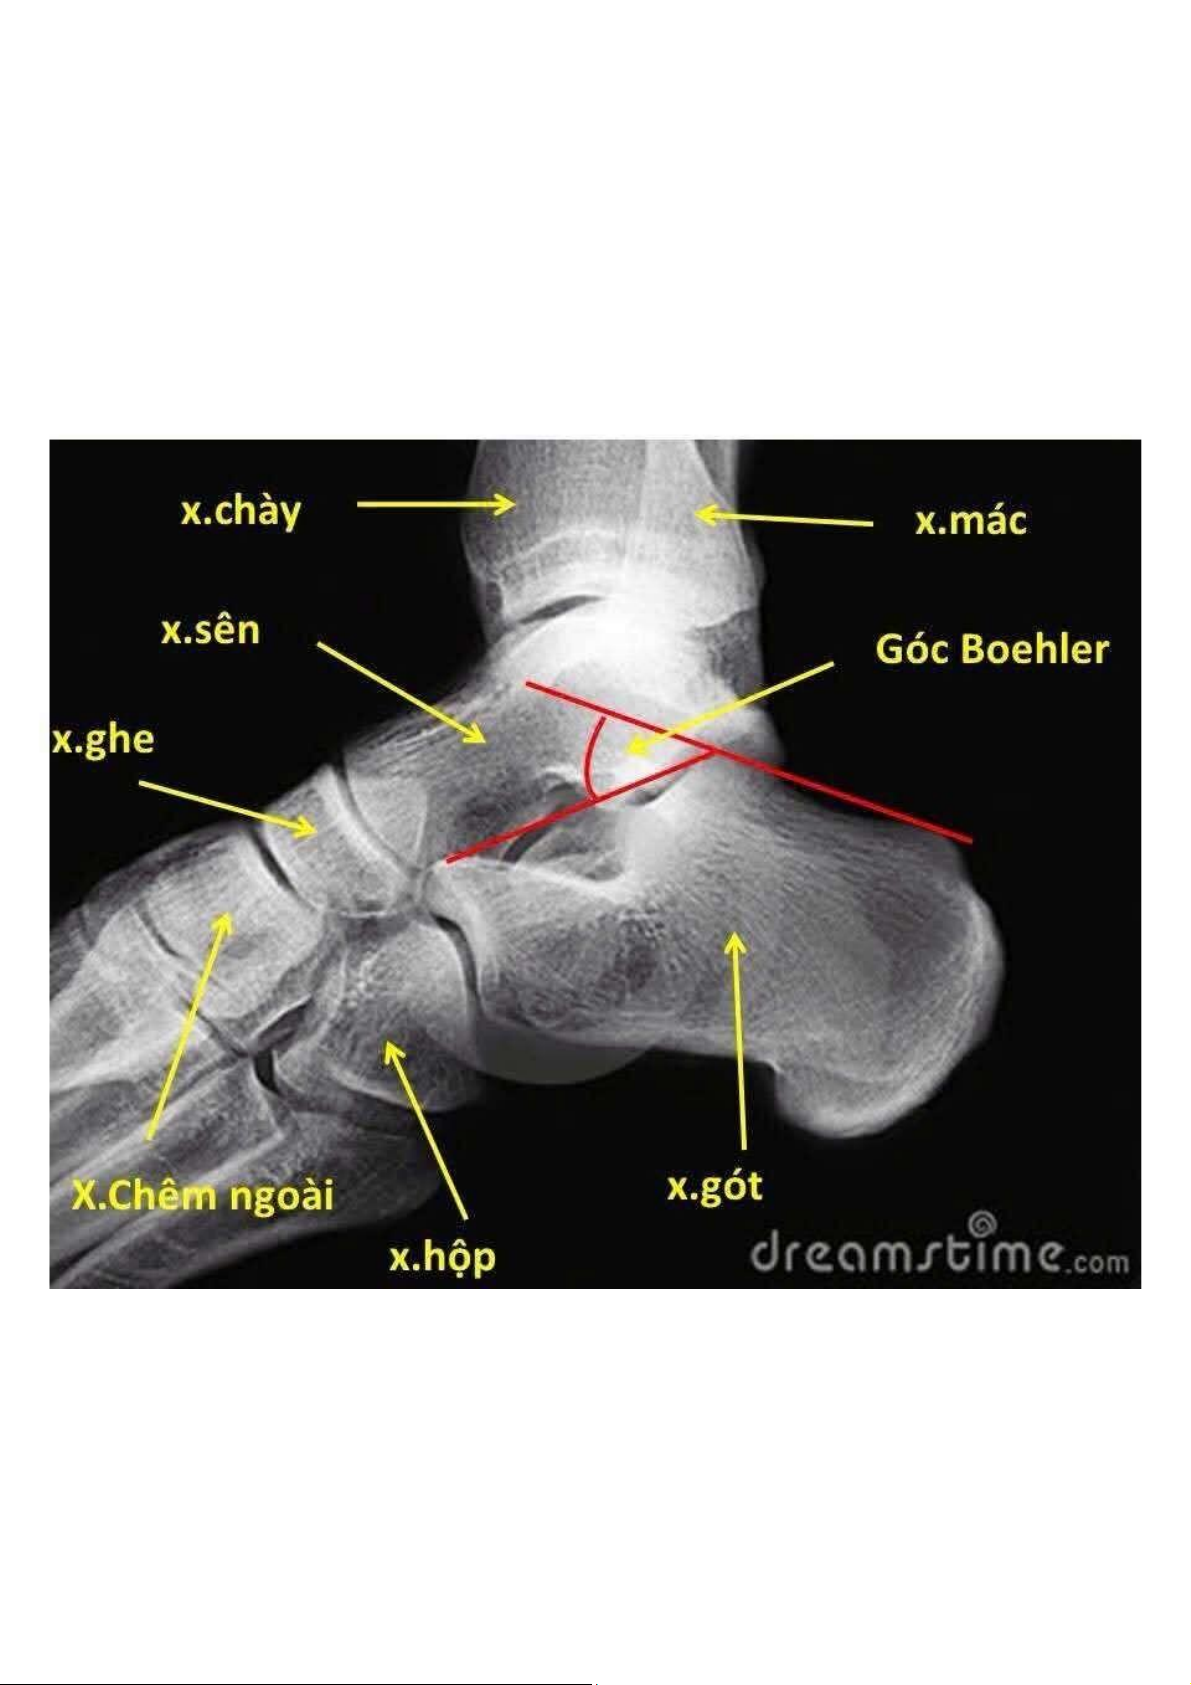

Gãy xương chày và mác dạng chồng ngắn. Gãy xương cánh tay dạng chồng ngắn và gập góp. Gãy xương quay dạng chồng ngắn và gập góp. Hẹp khoảng đĩa đệm. Xơ xương dưới sụn. Ngoài ra: kén dưới sụn, khí trong đĩa đệm, đóng vôi được dọc sau. Tài liệu giúp bạn tham khảo, ôn tập và đạt kết quả cao. Mời đọc đón xem!

Tài liệu Bài 6 X-Quang Xương Khớp - Phân Tích và Chẩn Đoán | Đại học Y dược Cần Thơ